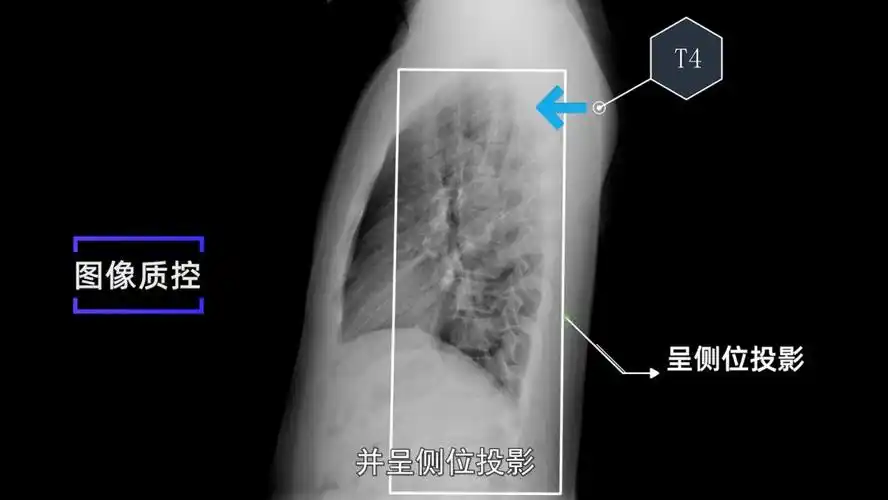

上图为正常胸部后前位片 上图是胸部侧位片的拍摄,一般采取右侧位